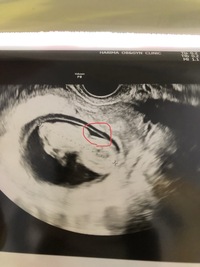

· その時のエコー写真がこちら。 丸がついている所が、疑わしき箇所です! しかし、エコーも鮮明じゃないせいか素人目には全然分からず・・・。 結局11週~12週では、性別の判明は諦めました。 19週のエコー写真 その後、性別が分かったのは19週の時です。 · 双子妊娠11週 りんごちゃんが心配 双子出産のために転院の手続きをして、ホームドクターが担当院としてつくようになりました。 カナダでの双子出産は少しややこしいのですが、だいたい3つの病院を行き来します。 ホームドクターがいるクリニック;妊娠11週目のお腹の大きさの写真&体重 妊娠11週0日目~妊娠11週6日目のお腹の大きさの写真と体重です。 写真を見ていただければわかると思うんですが、妊娠11週目は明らかにお腹まわりに脂肪がついてきた様子。 下腹部もさらにふっくらとしてきました。

妊娠11週0日目の2Dエコー写真がこちら↓↓ 胎児の大きさ(CRL):413cm そしてそして、妊娠11週0日目の4Dエコー写真がこちら↓↓ ちょっと見にくいかな? 上の2Dエコーの写真と同じ向きです。 写真だと白黒なんですが、実際はカラーで動いている映像が妊娠11週→外陰部の性差が決定しますが、超音波検査で性別が確認できるのは、16〜17週以降です。 妊娠10週の胎児の体重や母体の様子看護師が解説 18年5月27日 妊娠3ヶ月のエコー写真の様子 妊娠6週頃の赤ちゃんはとても小さくエコーではわかりにくく、心拍はまだ確認できません。 まだ

妊娠11週1日のエコー写真です 丸で囲んだところがntなのでしょ Yahoo 知恵袋

11週3日 Sakurashimaさん 32歳 11週3日のエコー写真 Crl 頭殿長 身長 または胎嚢の大きさ 47mm 体重 Bpd 頭の横幅 約4 7cm エコーでお顔 身体 手がわかるようになりました 目の位置からこちらを向いているようで もう可愛いです